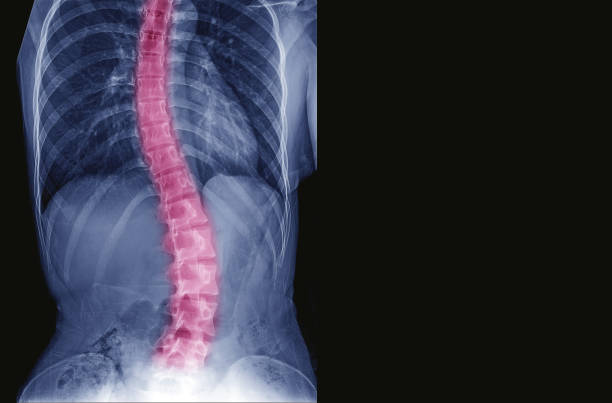

척추측만증은 허리가 옆으로 휘어진 상태를 나타내는 질환으로, 특히 청소년기에 많이 발생하는 허리의 변형이며 척추의 측만(옆으로) 휘어짐을 특징으로 합니다. 이 질환은 주로 10도 이상의 각도로 허리가 휘어질 때 측만증으로 분류됩니다.

척추측만증은 척추가 휘었다는 이야기 인데요. 많은 사람들이 이정도는 알고 있습니다.

하지만 조금 더 정확하게 어떤게 척추측만증인지 알지는 못합니다.